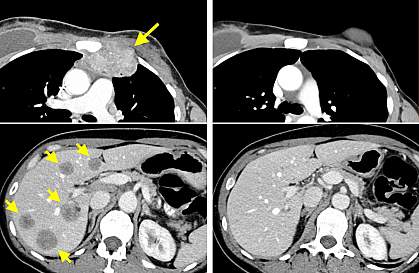

In an ongoing phase 2 clinical trial, a team led by Dr. Steven A. Rosenberg at NIH’s National Cancer Institute (NCI) has been developing a form of ACT using TILs that target specific tumor mutations. The team recently had success treating a patient with metastatic breast cancer who enrolled in the trial after receiving several treatments, including chemotherapy and hormonal treatments, that did not stop her cancer. The case report was published in Nature Medicine on June 24, 2018.

After this protocol, the patient’s cancer entirely disappeared. More than 22 months later, it hadn’t returned. The infused TILs were still found in the patient’s blood up to 17 months after the treatment.